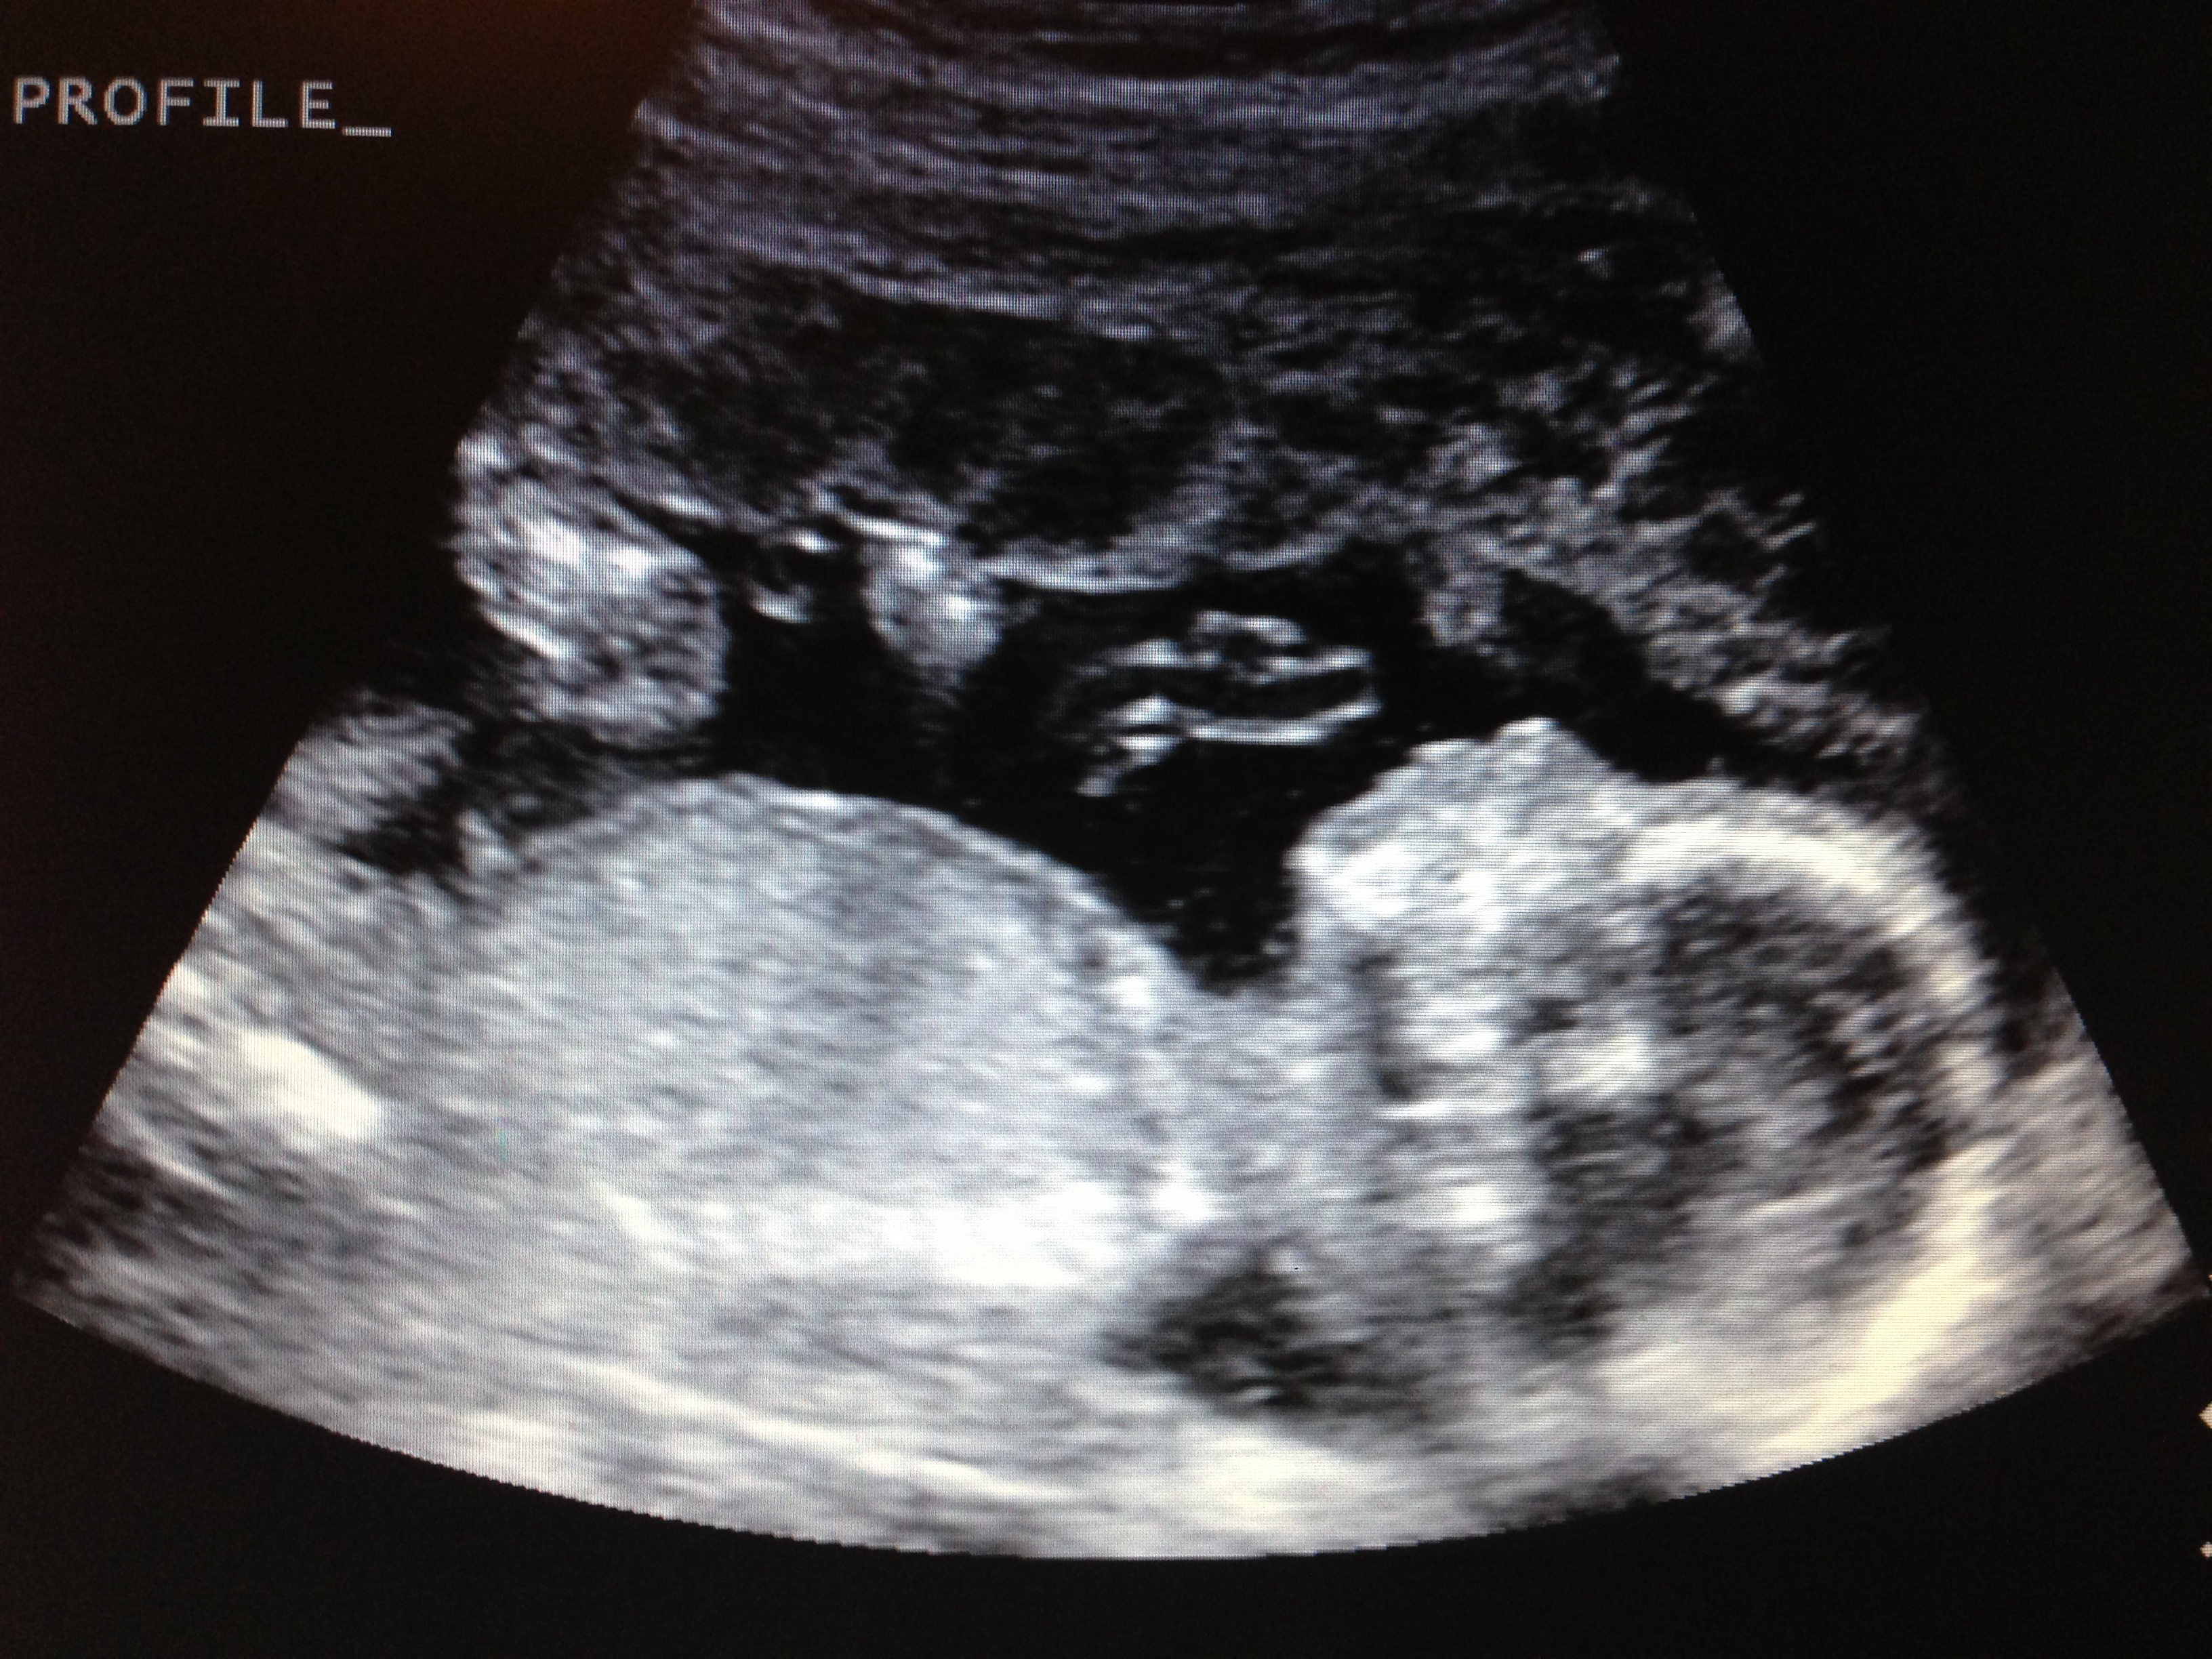

Photo from Sunday at 20 weeks. Profile of baby boy #3. I love that DH is able to feel this baby move more and more. Hoping within the next week or so, my boys will be able to feel it. He's getting really active in there!